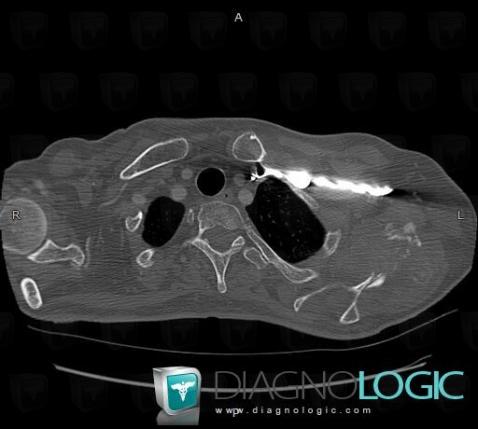

Metastasis, Scapula, CT

Here is the specific information in the key image above:

- Diagnosis Metastasis, Location(s) Scapula, with gamuts Ill-defined osteolysis, Cortical osteolysis, Expansive lesion